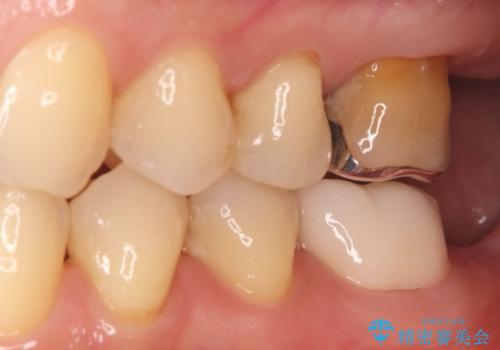

治療は、根管内の感染源を顕微鏡下で徹底的に除去・消毒する精密再根管治療から行いました。

根の状態が安定した後、金属を一切使用しないオールセラミッククラウンを装着しました。高い適合精度により二次感染のリスクを抑え、天然歯に近い透明感と耐久性を両立させています。根の違和感も解消され、機能・審美ともに健康な状態を取り戻しました。